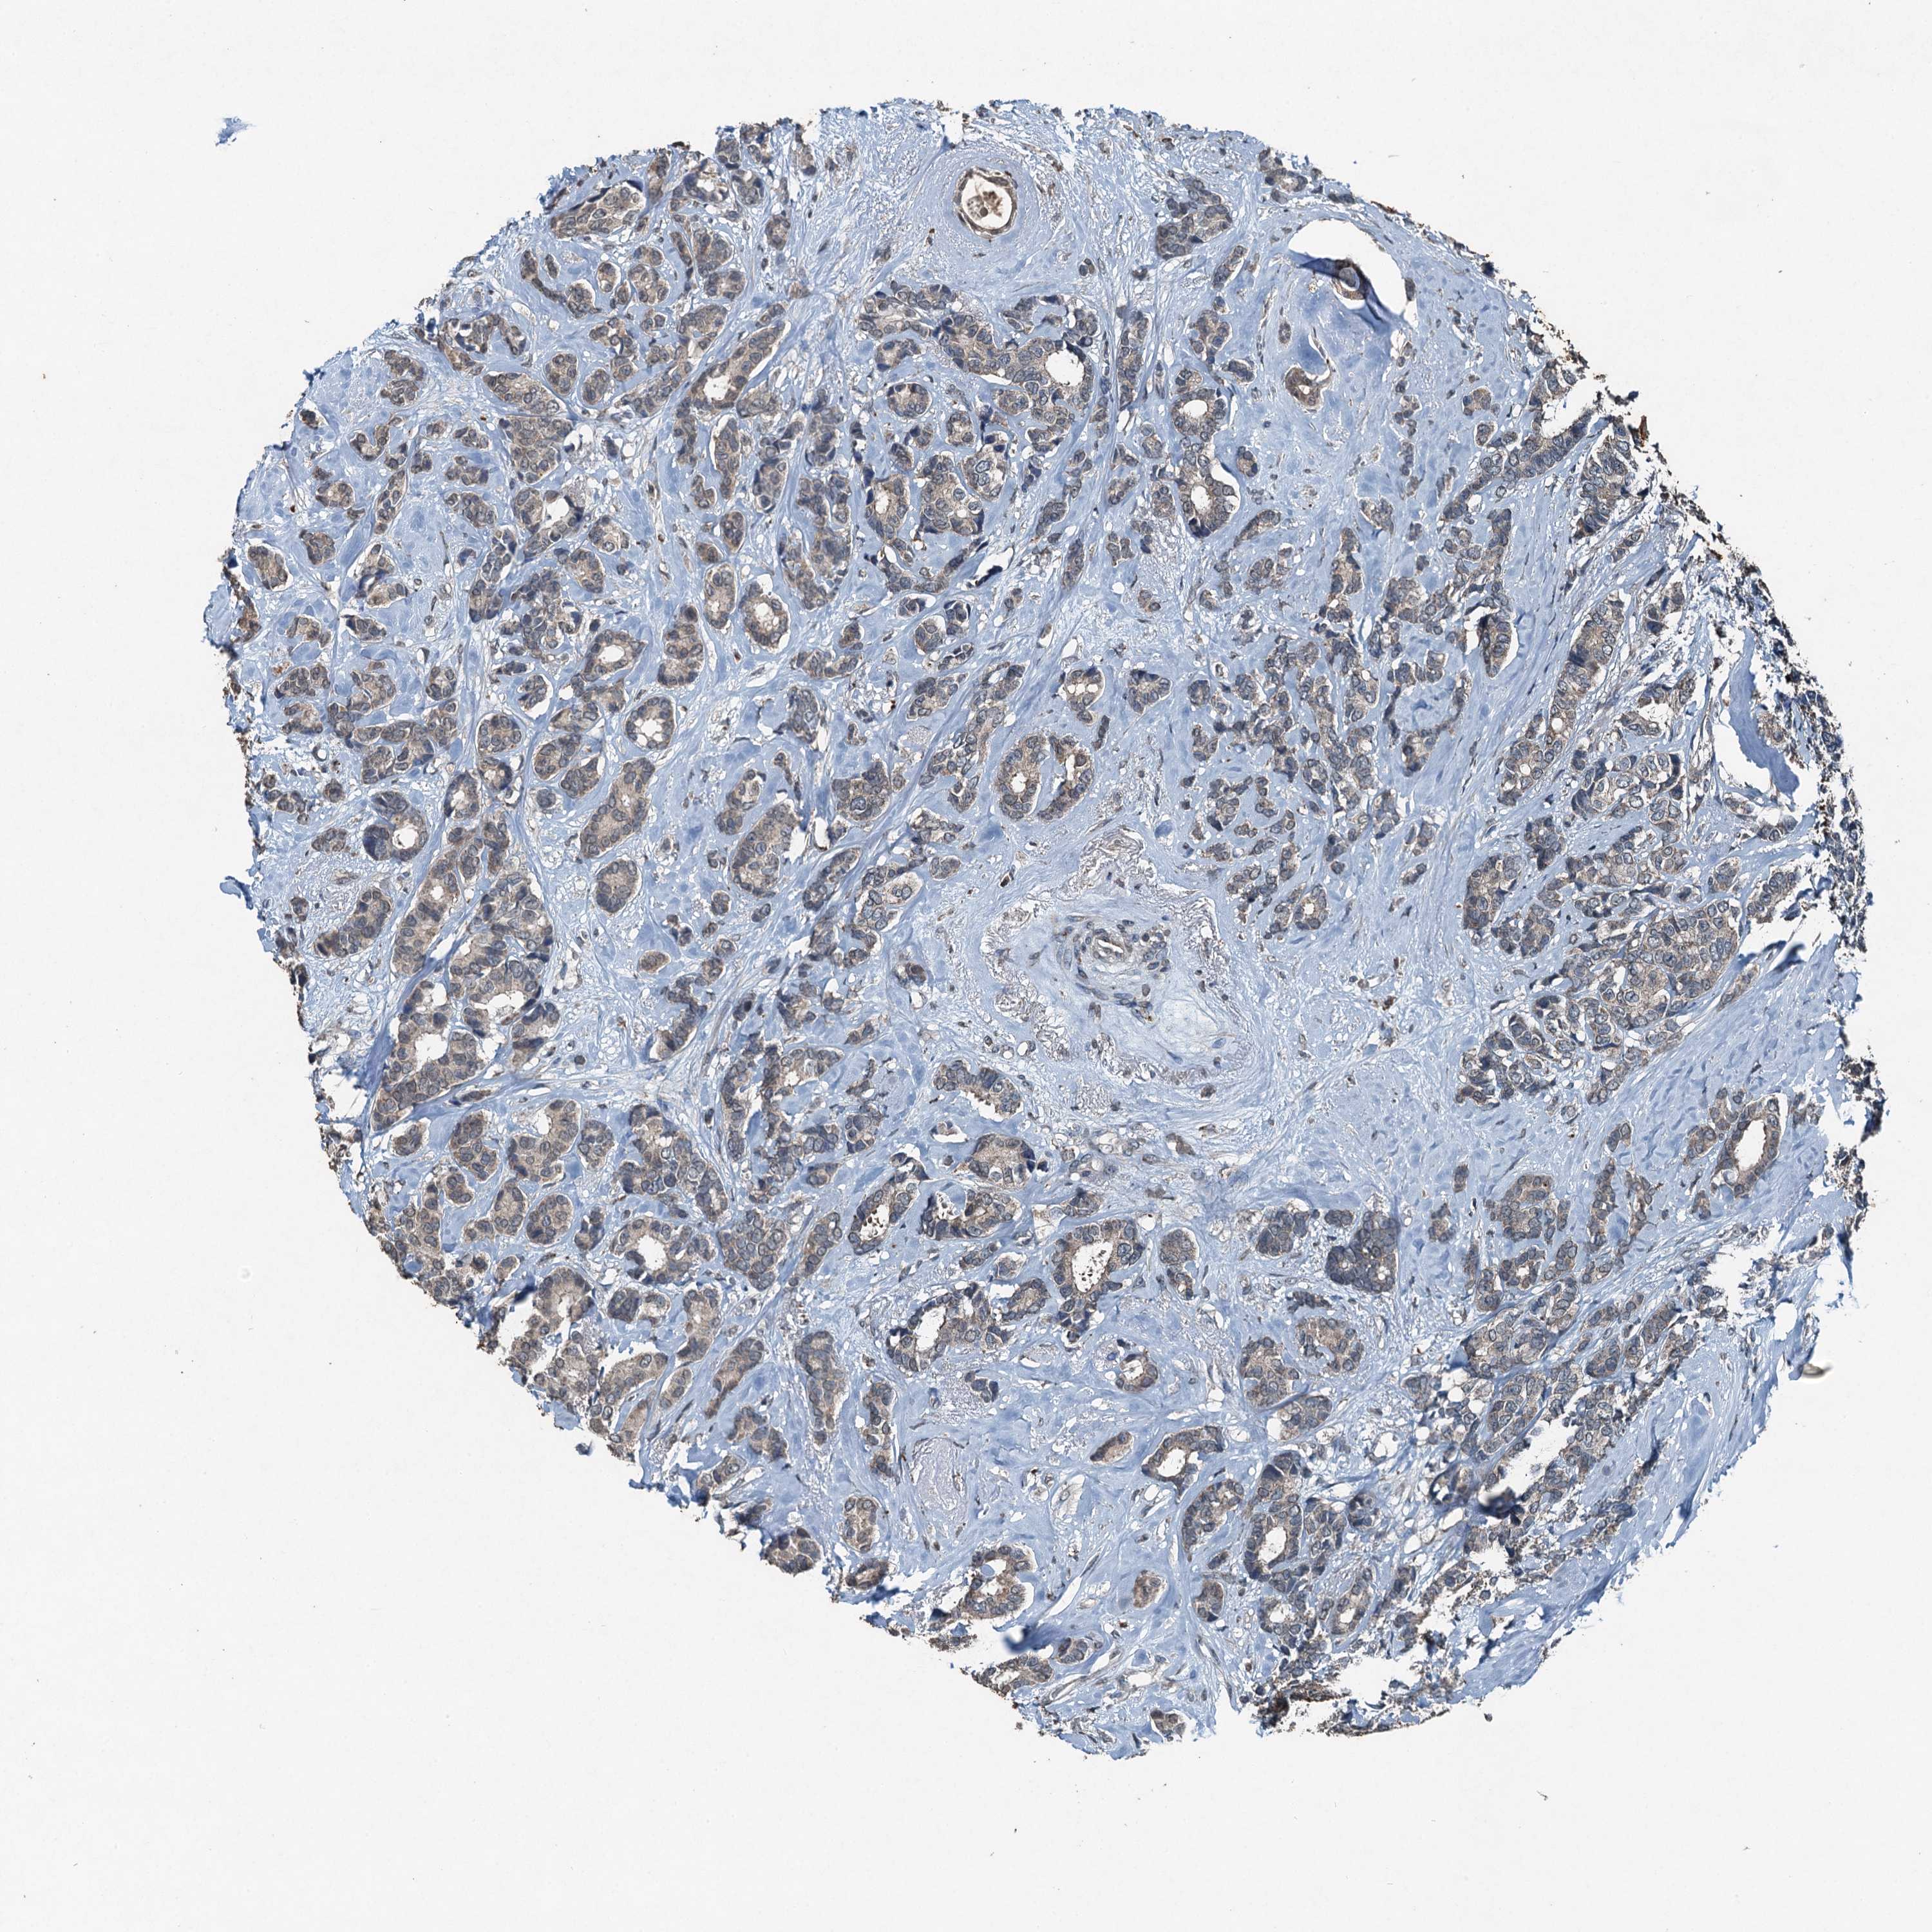

CANCER BREAST CANCER Show tissue menu

BRCA TCGA BRCA VALIDATION PROTEIN EXPRESSION